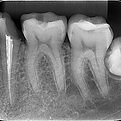

Radiografia periapical

É requisitada para a avaliação de uma única região ou dente.